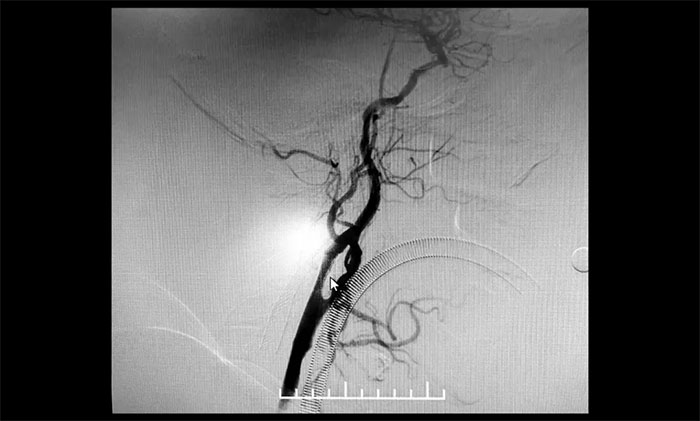

▲ 術(shù)后,左側(cè)頸內(nèi)動(dòng)脈狹窄明顯改善

術(shù)后康復(fù)觀察一月余,于耀宇主任團(tuán)隊(duì)再次為曹老伯行右側(cè)頸動(dòng)脈支架置入及左側(cè)椎動(dòng)脈支架置入手術(shù)。術(shù)中造影顯示,右側(cè)頸內(nèi)動(dòng)脈起始段重度狹窄,狹窄長(zhǎng)度8mm左右。左側(cè)椎動(dòng)脈 V4 段重度狹窄,長(zhǎng)度6mm左右。運(yùn)用嫻熟扎實(shí)的技術(shù),在充分做好腦保護(hù)的前提下經(jīng)過(guò)多次球囊擴(kuò)張后,順利釋放支架于狹窄處。造影提示支架打開(kāi)良好,血管狹窄基本恢復(fù)正常,支架貼壁佳,支架內(nèi)血流通暢,遠(yuǎn)端血流良好。

▲ 術(shù)后,右側(cè)頸內(nèi)動(dòng)脈及左側(cè)椎動(dòng)脈狹窄明顯改善